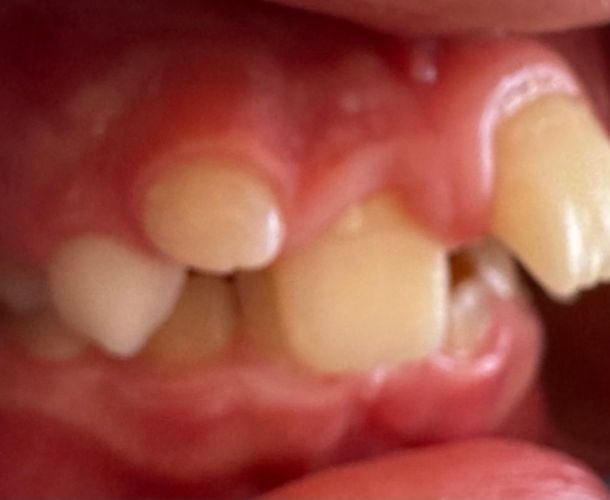

Medizin

Es ist erschreckend, wie viele Kinder heutzutage mit erheblichen Zahnfehlstellungen herumlaufen müssen. In meiner Praxis sehe ich häufig acht- bis elfjährige Kinder, die regelmäßig beim Zahnarzt und beim Kinderarzt waren, ständig wegen Karies behandelt werden und sich niemand über diese aggressive Kariesen…